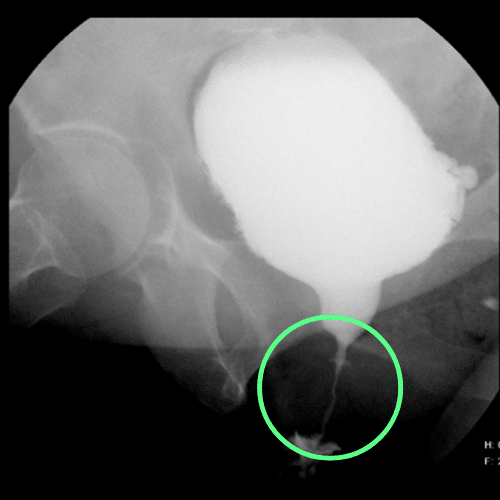

Imagen de cistouretrografía que revela una estenosis de la porción bulbar de la uretra de corta longitud

Cistouretrografía que revela una estenosis uretral en la zona bulbar de corta longitud (marcada con círculo)